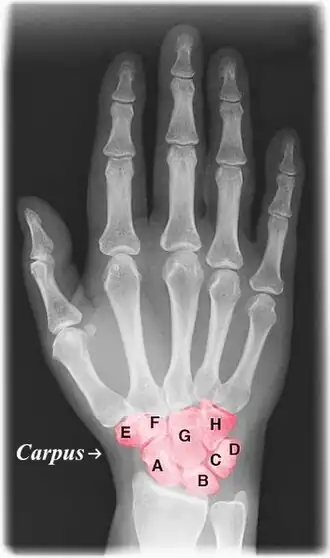

![]() Labelled image showing the eight carpal bones. | |

The carpal bones are the eight small bones that make up the wrist (carpus) that connects the hand to the forearm. The terms "carpus" and "carpal" are derived from the Latin carpus and the Greek καρπός (karpós), meaning "wrist". In human anatomy, the main role of the carpal bones is to articulate with the radial and ulnar heads to form a highly mobile condyloid joint (i.e. wrist joint),[1] to provide attachments for thenar and hypothenar muscles, and to form part of the rigid carpal tunnel which allows the median nerve and tendons of the anterior forearm muscles to be transmitted to the hand and fingers.

The eight carpal bones may be conceptually organized as either two transverse rows, or three longitudinal columns.

When considered as paired rows, each row forms an arch which is convex proximally and concave distally. On the palmar side, the carpus is concave and forms the carpal tunnel, which is covered by the flexor retinaculum.[2] The proximal row comprises the scaphoid, lunate, triquetral, and pisiform bones which articulate with the surfaces of the radius and distal carpal row, and thus constantly adapts to these mobile surfaces. Within the proximal row, each carpal bone has slight independent mobility. For example, the scaphoid contributes to midcarpal stability by articulating distally with the trapezium and the trapezoid. In contrast, the distal row is more rigid as its transverse arch moves with the metacarpals.[3]